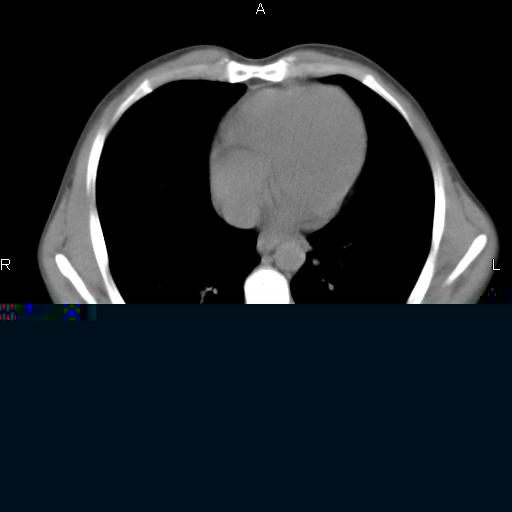

患者,男,40岁。间断发热,咳嗽二十余日。体温最高达38.9° 在当地诊所抗炎治疗三天后体温降至正常,患者自行停药。今又发热。胸片示,左下肺阴影。

左下肺片状高密度影,境界模糊,密度不均,考虑感染性病变可能性大,建议抗炎治疗后复查。左肺门增大,不除外占位性病变,必要时支气管镜检。